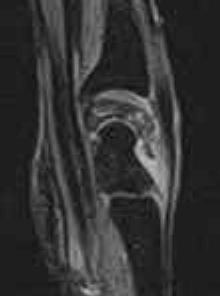

Stage IV:

There is degenerative arthrosis of the lunate and carpus. Hyperintense areas are not seen on the T2W, GRASS or STIR images and lunate collapse can be seen in all planes. Splaying of the volar and dorsal poles of the lunate is accompanied by extrinsic effacement and convex bowing of the flexor tendons in the sagittal plane. This may contribute to symptoms of carpal tunnel syndrome, especially if there is associated proximal migration of the flexor retinaculum with wrist shortening. Fragmented portions of the lunate usually demonstrate low signal intensity on T1W and GRASS images. Synovitis and radiocarpal effusion may be seen. Pannus tissue is low to intermediate in signal intensity on T1W and T2W images and enhances with gadolinium intravenous contrast. There may be wrist arthrodesis.